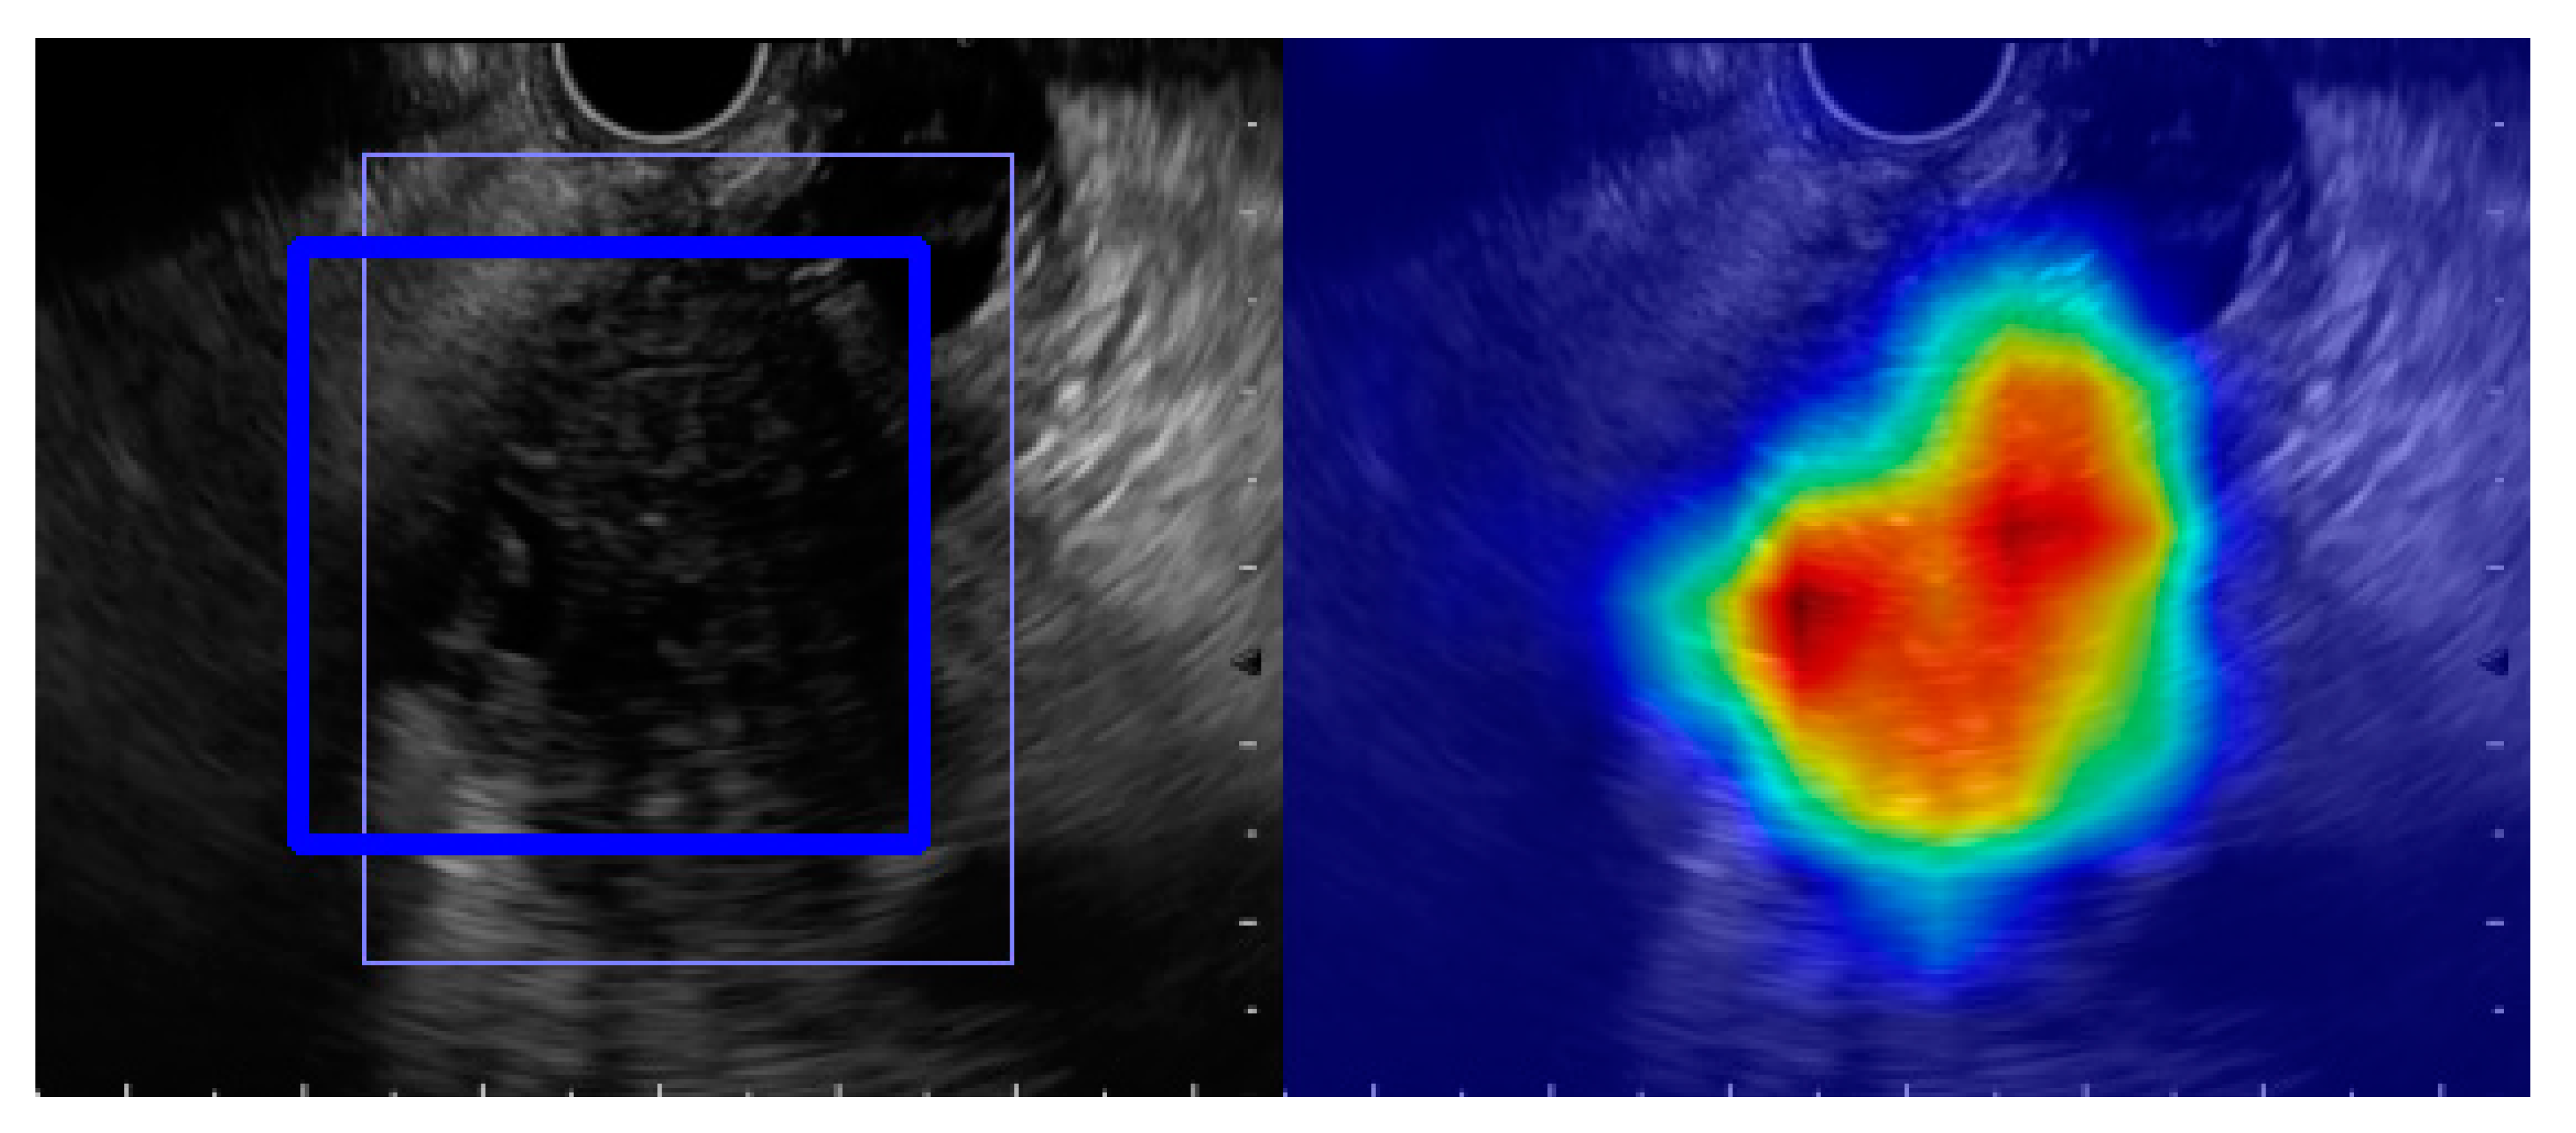

- Tonozuka, R.; Nagakawa, Y.; Nagata, N.; Kojima, H.; Sofuni, A.; Tsuchiya, T.; Ishii, K.; Tanaka, R.; Nagakawa, Y.; Mukai, S. Deep learning analysis for the detection of pancreatic cancer on endosonographic images: A pilot study. J. Hepato-Biliary Pancreat. Sci. 2020. [Google Scholar] [CrossRef] [PubMed]

- Selvaraju, R.R.; Cogswell, M.; Das, A.; Vedantam, R.; Parikh, D.; Batra, D. Grad-cam: Visual explanations from deep networks via gradient-based localization. In Proceedings of the IEEE International Conference on Computer Vision, Venice, Italy, 22–29 October 2017; pp. 618–626. [Google Scholar]

| Tonozuka R [40] | 2020 | Detection of PC | 139 | B-mode image | Deep Learning based CAD | CNN |